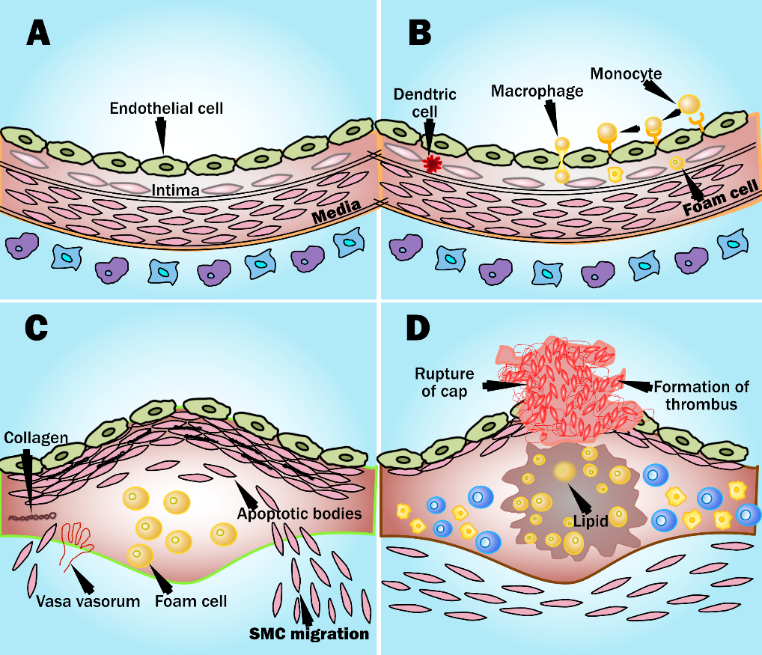

With prolonged exposure to risk factors, it is observed that early fatty streak development begins in childhood and adolescence. Further, early fibroatheroma occurs in the population in their teenage and young adulthood years [101, 102]. Fig. 6 shows the development of an atherosclerotic lesion in the inner lining of an artery.

Fig. 6.

Fig. 6.Development of atherosclerotic lesion.

The initiation of the fatty streak phase of atherosclerosis begins with dysfunctional endothelial cells and the retention of apoB-containing lipoproteins in the sub endothelial space. It is seen that chronic endothelial injury is caused by various factors, including hyperlipidemia, hypertension, smoking, homocysteine, hemodynamic factors, toxins, viruses, or immune reactions. Injury in the endothelial-related region contributes to antithrombotic properties that facilitate the platelet adhesion and activation of the dysfunctional area [10]. The lipoproteins are then modified by the process called oxidation at the extracellular matrix of the subendothelial space [103]. Further, modified LDL promotes the activation of endothelial cells (EC) and smooth cells (SCM) and starts the recruitment of immune cells (i.e, monocytes) into the endothelial layer. These recruited immune cells cause a reduction in nitric oxide inside the endothelial wall resulting in endothelial dysfunction, which further triggers the atherosclerosis process [104]. Collectively, an increased monocyte interaction further differentiates into macrophages and leads to the internalization of VLDL, modified LDL, and apoE remnants. This leads to the formation of foam cells [105].

The foam cells are cholesterol-containing lipid-laden macrophages that lead to the formation of plaque. The endothelial dysfunction begins as atheroma or benign tumors of smooth muscle cells within the blood vessels. It is characterized by increased permeability, leukocyte adhesion, monocyte adhesion, and emigration. Progression of atherosclerotic plaque is seen when numerous macrophage foam cells and other inflammatory cells continue to promote the formation of other monocytes and immune cells.

The proliferation of tunica-media smooth muscle cells leads to the formation of the fibrous fatty lesion [106]. Vaso Vasorum neovascularization exists in atherosclerosis as a compensatory reaction to provide adequate nourishment and oxygen to atherosclerotic arteries [107]. The developing lesions sometimes represent the next stage beyond fatty streaks and are pearly plaque with dome shape appearance often referred to as “cap”. These lesions may further advance and can be represented as calcified fibrous areas of arteries along with visible ulceration [108]. The plaque, which is covered with a thick fibrous cap and has a well matured necrotic core, is referred to as stable plaque. This fibrous cap proves as an effective barrier in preventing plaque rupture and exposure of prothrombin factors in the vascular pathway [109]. An observation of atherosclerosis is that the macrophage cholesterol pathway becomes inefficient, leading to an imbalance in the lipid metabolisms and cholesterol, further progressing to the disruption of cellular functions [110]. Vulnerable plaque is a result of the unresolved and heightened inflammatory status of the lesions of foam cell core. Data reported in a study indicated that some nutritional and toxic trace metals may have a role in the progression or rupture of plaque [111]. Rupture or erosion of the advanced lesion initiates platelet activation and aggregation on the surface of the disrupted atherosclerotic plaque (see Appendix Fig. 13). Thrombotic vascular occlusion is associated with ischemic episodes, including acute coronary syndromes or cerebral infarction [112].

Fig. 13.

Fig. 13.Atheroma development and plaque rupture (courtesy of AtheroPoint, Roseville, CA, USA). (A) Healthy blood vessel with no change in the geometry of the endothelial layer. (B) Penetration of monocytes in the intimal layer. (C) Formation of plaque with foam cells and migration of smooth muscle cells. (D) Atherosclerotic plaque rupture and formation of thrombus.